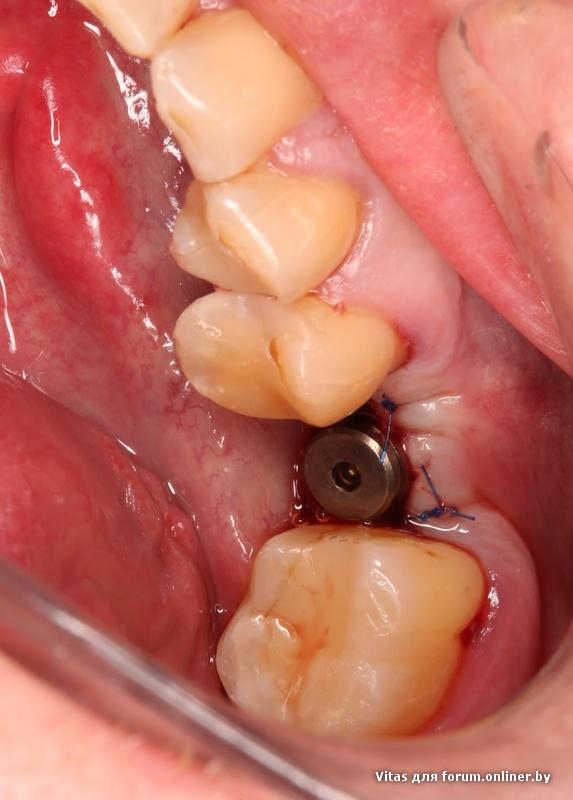

Для любителей кровавых фото.

На бруксизм не обращайте внимания.

чего эта фотка онлайнером переворачивается не понятно....

Записался к своему хирургу)

Имплант альфа Био 3.75*13... Решили с 3.75*16 не рисковать... До нерва 1мм остается.